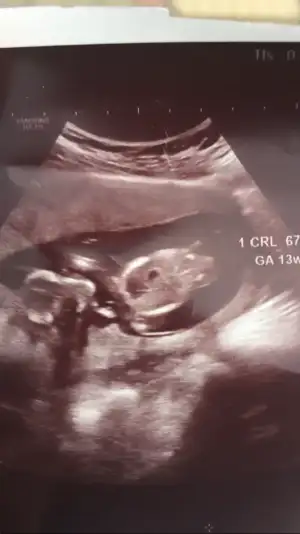

Merhaba 12+1 günlüğüz doktor emin olamadı ama erkek demiştiniz 11 haftalıkken şimdi ne görünüyo acaba bacak arasında bişeyler var gibi 😌

Eklentiler

• 215A4D6D-6E97-4003-9F32-BEC028E95D56.webp

215A4D6D-6E97-4003-9F32-BEC028E95D56.webp